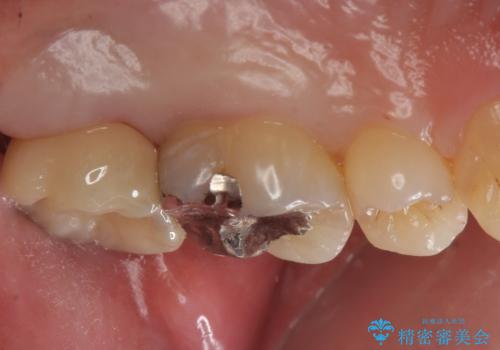

- 奥歯のザラザラが気になり、白い被せ物をしたいとのことで来院。

レントゲンや拡大鏡で確認をしたところ歯の表面は粗造になっていたが

う蝕があるわけではないので以下の提案を行った。

歯の表面が粗造なのは虫歯ではないが

歯の表面が溶けはじめて、虫歯になりやすい状態になっています。

銀の詰め物のやりかえも検討されています。